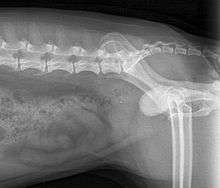

When symptoms indicate bladder stones, the first step is usually to take an x-ray. Most types of stones will appear readily in an x-ray, urate and occasionally cystine stones being the most common exceptions. Stones smaller than three millimeters may not be visible.[3] Ultrasonography is also useful for identifying bladder stones. Crystals identified in a urinalysis may help identify the stones, but analysis of the stones is necessary for identification of the complete chemical composition.